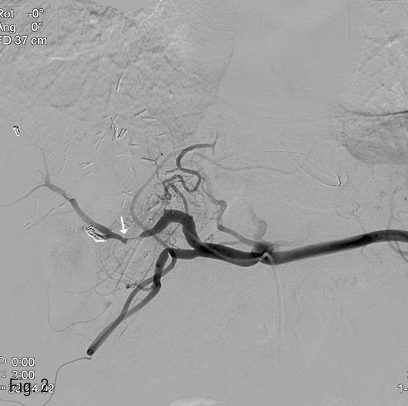

우측 대퇴동맥을 Seldinger method로 천자한 뒤, 6Fr sheath (Accu-sheath, SungWon Medical, Cheongju, Korea)를 삽입하였다. 0.035”유도철선 (Radifocus guidewire M, Terumo corp., Tokyo, Japan)과 Yashiro catheter (RHR, Cook Medical, USA)를 이용하여 복강동맥을 선택하여 혈관조영술을 실시하였다. 복강동맥조영술에서 고유간동맥의 불규칙한 혈관내경 감소와 낭성 돌출을 보이는 혈관병변이 관찰되어 내시경에서 보인 가성동맥류로 판단하였다. (Fig. 2). 이 병변에 스텐트 그라프트를 설치하기 위해 8Fr angio sheath(Accu-sheath, SungWon Medical, Cheongju, Korea)로 교체한 뒤, 같은 방법으로 Yashiro catheter를 고유간동맥까지 진입시킨 상태에서 0.035” 유도철선 (Radifocus Guidewire M, Stiff type, Terumo corp., Tokyo, Japan)을 우간동맥까지 조심스럽게 진입시켜두고, 병변부에 말초혈관용 스텐트 크라프트 (6mm x 4cm, Hercules Vascular Stent-graft, S&G Biotech, Seongnam, Korea)를 설치하였다. 설치 직후 병변부 주변으로 일시적인 혈관연축이 관찰되었으나, 전반적인 관류 상태는 양호하였으며, 혈관병변들이 호전된 것을 확인할 수 있었다(Fig. 3).

Fig 3

After the placement of peripheral vascular stent graft, the pseudoaneurysm is successfully treated and transient vascular spasm (arrow) is noted nearby the stent graft.